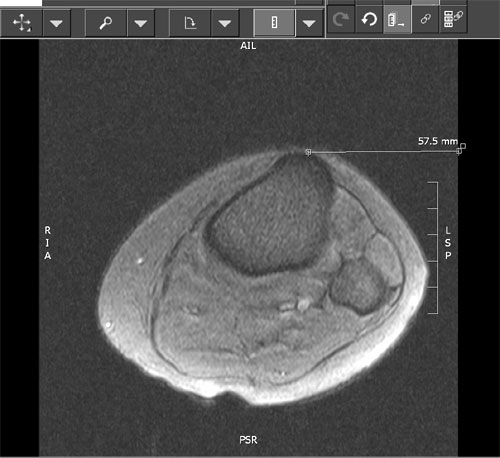

The patellotrochlear index laves på basis af MR skanning:

Index: BL(P)/BL(T)*100= index: <12,5%= Patella alta. >50% = Patella infera